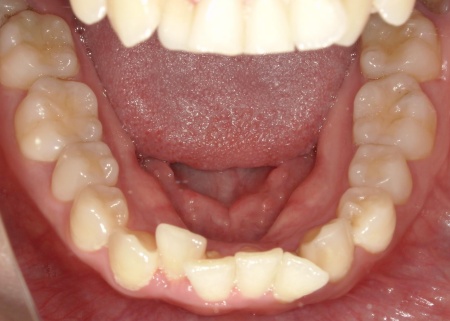

20代女性 八重歯と歯並びの乱れをマウスピース矯正装置で改善した症例

「上下の八重歯が気になる」とご相談いただきました。

拝見したところ、歯が正しく並ぶためのスペースが不足しており、歯が重なって生えてしまう叢生(そうせい)の状態が全体的に見られました。

特に上下の糸切り歯が外側にずれている、いわゆる八重歯が目立っています。